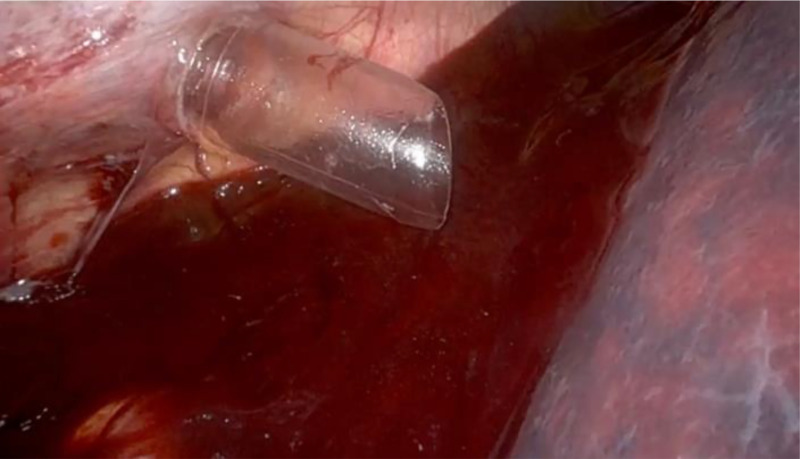

Case description: A 36-year-old female with a history of recurrent catamenial pneumothorax and two prior video-assisted thoracoscopic surgeries to treat diaphragmatic endometriosis presented to our clinic with right-sided shoulder pain and a chest tube in place. She underwent robotic-assisted laparoscopic pelvic and bowel resection for severe endometriosis and liver mobilization to repair the right diaphragm. During liver mobilization, the surgeon inadvertently caused a 2-mm defect in the suprahepatic IVC, resulting in 250 mL of venous hemorrhage. Hemostasis was achieved using robotic compression of a fibrin sealant patch, avoiding conversion to laparotomy. The chest tube was maintained throughout surgery and postoperatively for drainage. The patient experienced no thrombotic complications.

Discussion: This case illustrates the successful use of a fibrin sealant patch to control a major vascular injury in the robotic-assisted laparoscopic setting. While fibrin sealant patches are Food and Drug Administration-approved for soft tissue hemostasis, their application in major vascular repairs, including the IVC, is off-label. The blood loss (250 mL) and absence of thrombotic events highlight the safety and efficacy of the fibrin sealant patch. Further investigation is warranted to establish the efficacy of fibrin sealants in the repair of major vascular injuries in robotic-assisted and traditional laparoscopic surgeries.